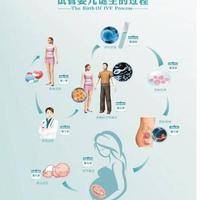

试管婴儿技术,在医学方面称为试管受孕-胚胎移植,是一种将卵子和精子取出体外,在实验室特殊环境中完成受精过程,再将构成的胚胎移植回母体子宫内发育的助孕方法。这一项技术主要适用于输卵管因素导致的不孕、男性精子质量问题、子宫内异症患者,以及缘由不明的不孕情况。

目前主流的试管婴儿技术分为三种:一代技术主要解决女性输卵管问题,让精卵在体外自在结合;2代技术针对男性精子问题,通过单精子注射方式强行做到受精;三代技术则是在胚胎移植前进行遗传生物学筛查,有效预防遗传性疾病传递,实现优生优育。

试管婴儿技术助孕整个过程约需两到三个月时间。前期筹备阶段囊括基础检查如性激素六项、精液分析、AMH值检测等,须要1-2周。随之是促排卵阶段,医生会根据个人情况制定方案,促进多个卵泡同时发育,此阶段需要按期B超监测卵泡生长情况。

取卵和取精通常在同日进行,取出的卵子和精子在实践室中进行受精和培养。胚胎培养三至五天后,医生懂得挑选择一至两个优质胚胎移植入子宫。移植后仍旧要黄体支持治疗,约14天后即可进行妊娠检查。